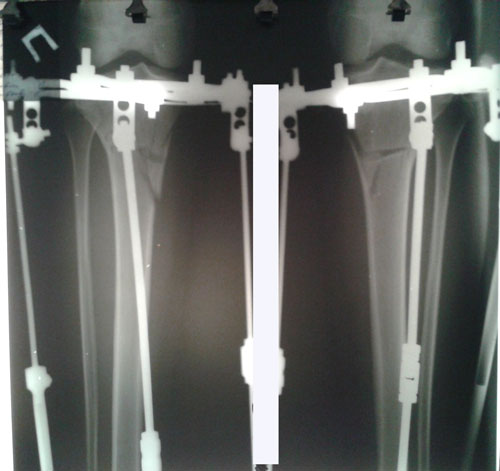

Дата операции 04.12.2015г.

Исходник - 26 лет.

Не смотря на молодой возраст, у пациентки начальная стадия артроза.

рентген до операции